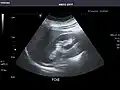

Right kidney -

Kidneys: Right and left kidneys measure 11.5 cm and 12 cm in length respectively. No hydronephrosis. Small left lower pole kidney cyst.